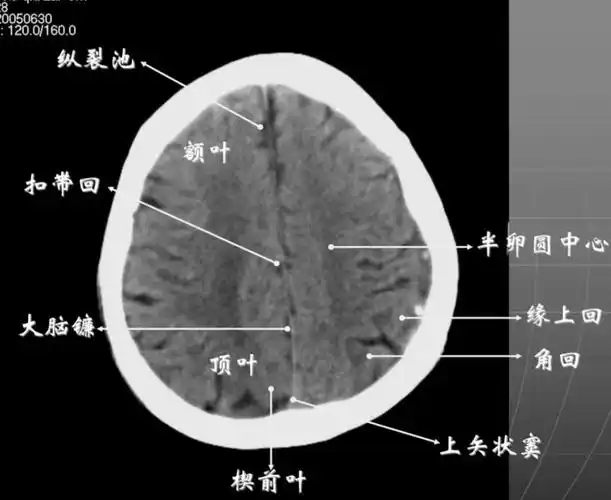

颅脑断面解剖ppt 医学影像学 头颅 诊断 ct 颅脑断面解剖 半卵圆中心

8大脑皮质上部层面(半卵圆区上部层面)已近颅顶,大脑镰清晰可见,其旁